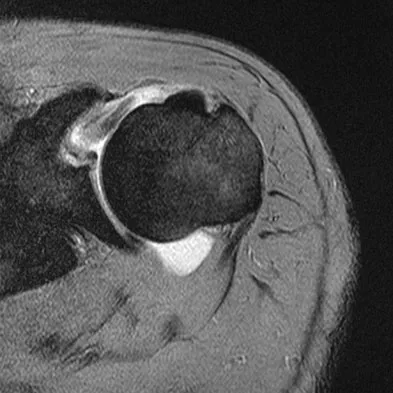

A 47-year-old male tennis player has pain in his nondominant shoulder that has failed to respond to 4 months of nonsurgical management. Examination reveals acromial tenderness and pain at the supraspinatus tendon insertion. He has a positive impingement sign, pain on forward elevation, and minimal cuff weakness. The MRI scans are shown in Figures 30a and 30b. To completely resolve his symptoms, treatment should consist of

The MRI scans show a mesoacromion with tendonopathy of the supraspinatus. The history and physical findings indicate that the patient has a symptomatic os acromiale. Simple excision of the unstable os acromiale has not yielded consistently good results. Meticulous internal fixation using tension banding with cannulated screws and autologous bone grafting has shown good results for this problem. Hutchinson MR, Veenstra MA: Arthroscopic decompression of shoulder impingement secondary to os acromiale. Arthroscopy 1993;9:28-32.

- Warner JJ, Beim GM, Higgins L: The treatment of symptomatic os acromiale. J Bone Joint Surg Am 1998;80:1320-1326.